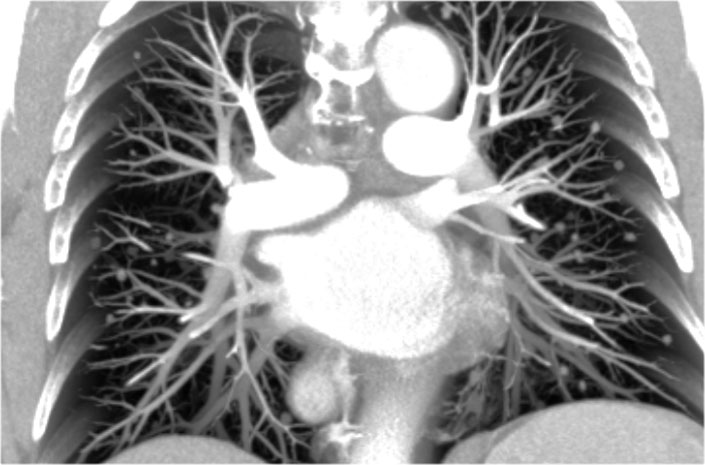

Hili

The normal hilar shadow on chest radiography is predominantly vascular in nature—comprising approximately 99% of pulmonary arteries and, to a lesser extent, pulmonary veins (1).

These vascular structures have well-defined, smooth margins and demonstrate normal branching patterns.

Image

Thick coronal slab MIP at the level of the hili.

An important anatomical consideration is that the left hilum is normally situated higher than the right.

This relationship arises from the course of the pulmonary arteries: the left pulmonary artery arches over the left main bronchus, while the right pulmonary artery courses anterior to the right main bronchus, which is typically positioned lower than its left counterpart.

In a minority of cases, the hila may be at the same level, but the right hilum should never be higher than the left.

In this illustration, lower lobe pulmonary arteries are colored blue to indicate deoxygenated blood.

These arteries have a more vertical orientation compared to the pulmonary veins, which run more horizontally toward the left atrium, located inferior to the level of the main pulmonary arteries.

On lateral chest radiographs, both pulmonary arteries and veins are identifiable and should not be misinterpreted as lymphadenopathy. Occasionally, pulmonary veins may appear prominent.

The left main pulmonary artery passes superior to the left main bronchus and lies higher than the right pulmonary artery, which courses anterior to the right main bronchus.

The included images are thick-slab sagittal CT reconstructions of the thorax, which enhance visualization of hilar structures.

The lower lobe pulmonary arteries descend from the hilum in a vertically oriented fashion.

Radiographically, these vessels are colloquially referred to as the “little finger” due to their size and shape, approximating that of a little finger (1).

On PA chest radiographs, the "little finger" of the right lower lobe pulmonary artery is visible in approximately 94% of normal individuals, while on the left side it is visible in about 62% (1).